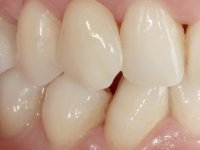

To define the dental zone to be covered by the Maryland bridge retainers, the patient was asked to perform maximum intercuspidation movements, and the contact points were marked with articular paper. Tooth preparation of the interproximal surfaces was made, to create a prosthetic insertion axis. It was sought that the mesio-distal diameter at the incisal level was equal to the diameter mesio-distal at the cervical level, that is to say, the interproximal walls were parallelized. Tooth preparation was done with fine grain diamond drills, and later polishing was done with abrasive discs. Color information was collected even before confection of the impression, to avoid dehydration of the arcade. Definitive impression was made using wash technique impression with silicone of heavy and regular consistency, both with fast setting, and a working plaster model was prepared in the lab. A laboratory scanner was used to scan the working model, and later, the infrastructure for the Maryland bridge was made using a CAD-CAM process. Ceramic was placed on this subframe. A ceramic adhesive was applied to the internal surface of the wings and connectors, which would enable bonding to the adjacent teeth. The adhesive bridge was bonded in the mouth following the conventional bonding technique. After bonding, the protrusion and laterality movements were carefully checked to avoid undesirable contacts.